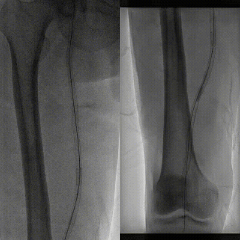

图:术后造影示股腘动脉、腓动脉及足部动脉显影好

图:术中CT

手术结果

图:术后效果